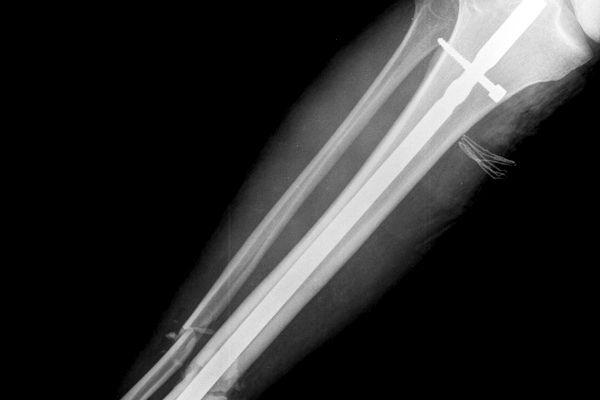

Gabinet ortopedyczny prowadzony przeze mnie specjalizuje się w leczeniu schorzeń i urazów kończyn górnych i dolnych. Zajmuję się leczeniem choroby zwyrodnieniowej stawu biodrowego i kolanowego, uszkodzeń wewnętrznych stawu kolanowego i barkowego, złamań w obrębie kończyn górnych i dolnych oraz urazów ścięgien i mięśni kończyn górnych i dolnych. Ponadto wykonuję diagnostykę USG narządu ruchu i badanie preluksacyjne (USG bioderek niemowląt). Leczę również neuropatie uciskowe kończyn (zespół kanału nadgarstka, rowka nerwu łokciowego, kanału Guyona) oraz uszkodzenia wewnętrzne stawów kończyn górnych i dolnych. Zapraszam do mojego gabinetu, gdzie dobiorę odpowiednie do schorzenia metody leczenia i zakwalifikuję do ewentualnego leczenia operacyjnego. W celu umówienia się na wizytę proszę o kontakt telefoniczny z rejestracją gabinetu ortopedycznego w Lesznie.